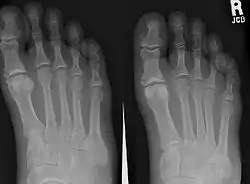

Para el diagnóstico debe tenerse en cuenta la sintomatología y los hallazgos radiológicos (radiografías anteroposterior, lateral y oblicua de los pies).